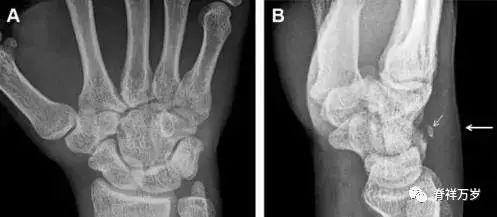

30.桡骨远端骨折

常规进行前后位、侧位、斜位 X 线检查,对于大多数桡骨远端骨折来说不容易漏诊;但是对于无移位的骨折,特别是桡骨茎突骨折,容易漏诊。桡骨茎突骨折是一斜行的骨折,常累及关节面,常发生于轴向应力或直接打击。

图 1 57 岁女性,摔倒后手掌撑地,桡骨茎突压痛。(A~C)前后位、斜位、侧位片示软组织肿胀(*)和发丝样骨折(白色箭头);(D~F)2 周后,前后位、斜位、侧位片示骨折线显明,由于新骨痂沉积而呈现透亮线与硬化线并存;(G~I)另一患者,桡骨茎突骨折在前后位及侧位片上显示不明显,而在斜位片显示更清楚。

31.舟状骨骨折

舟状骨骨折 60%~70% 发生于腰部,15% 发生于近极, 10% 发生于远极, 8% 发生于远端关节面。除了常规的前后位、侧位、斜位片外,还需要拍专门的舟状骨位片(腕关节尺偏,以舟状骨为中心的腕关节前后位片),特别是鼻烟壶有压痛时。

图 2 舟状骨骨折 (A、B)第 1 例患者,舟状骨远极关节内骨折(白色箭头),斜位片显示较清楚(B);(C、D)第 2 例患者,舟状骨腰部骨折(虚线箭头),斜位片显示较清楚(D);(E~H)第 3 例患者,舟状骨近极骨折,常规 X 线片均未看到骨折,而在舟状骨位片上才能见到骨折(虚线圆)。